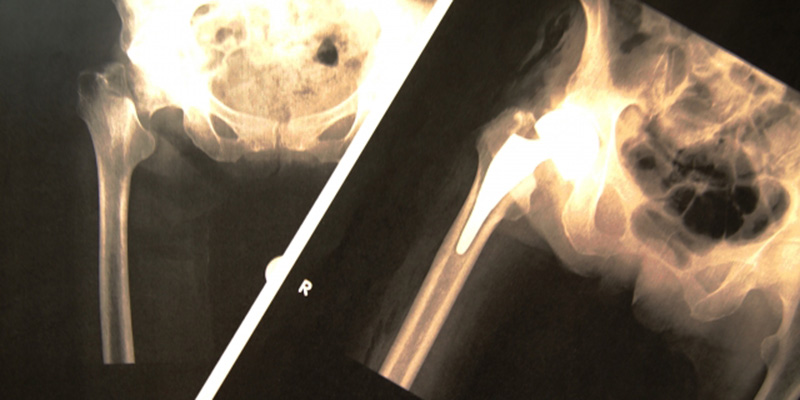

- 足(大腿骨骨折)

桝谷さんのけがは右大腿骨骨折です。9か月の入通院をしたものの、完治せずに症状固定となりました。

弁護士が後遺障害の手続きをしたところ、右大腿骨骨折後の足の痛みについて「局部に神経症状を残すもの」(14級9号)となりました。